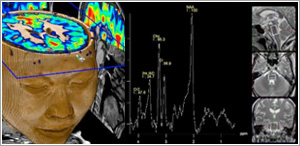

MR Spectroscopy (MRS)

MRS is a relatively new clinical procedure that allows detection of biochemical abnormalities within the brain. It is generally performed in addition to an MRI scan.